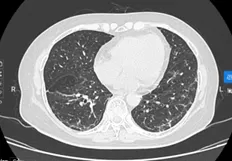

BN nữ P.T.H, sinh năm 1967, nhập viện vào thời điểm tháng 04/2024 vì lý do ho khan kéo dài, khó thở khi gắng sức, kèm theo đau nhiều cột sống ngực, thắt lưng. Kết quả kiểm tra ban đầu cho thấy hình ảnh tổn thương u phổi nhiều khối lan toả 2 phế trường, kèm theo di căn xương đa ổ. Kết quả sinh thiết vào vị trí u thuỳ dưới phổi phải là ung thư biểu mô tuyến phổi, xét nghiệm giải trình tự gen thế hệ mới NGS phát hiện đột biến xoá đoạn trên exon 19 gen EGFR (del19/EGFR). Bệnh nhân được lựa chọn liệu pháp nhắm đích ưu tiên là thuốc nhắm đích EGFR-TKI thế hệ 3, sau 6 tuần điều trị, tổn thương phổi 2 bên đáp ứng gần hoàn toàn trên CLVT ngực, bệnh nhân giảm đau rất nhiều tại tổn thương di căn xương cột sống, có thể sinh hoạt đi lại được, hoàn toàn không còn triệu chứng cơ quan hô hấp như ho hay tức ngực, khó thở.

Hình 7: tổn thương phổi sau 06 tuần điều trị và hình ảnh hiện tại

Còn rất nhiều ca bệnh UTPKTBN sau điều trị với liệu pháp nhắm đích đã đạt được “kỳ tích” ngoạn mục, 02 ca lâm sàng trên đây là số ít ca được chia sẻ kèm dẫn chứng minh hoạ về hình ảnh để quý bạn đọc có thể hình dung một cách sinh động hơn về hiệu quả diệu kỳ của liệu pháp ít độc tế bào này.